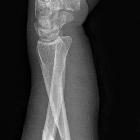

Galeazzi fracture-dislocation

Galeazzi fracture-dislocations consist of fracture of the distal part of the radius with dislocation of distal radioulnar joint and an intact ulna. A Galeazzi-equivalent fracture is a distal radial fracture with a distal ulnar physeal fracture .

Galeazzi fractures are classified according to the position of the distal radius:

- type I: dorsal displacement

- type II: volar displacement

Plain radiograph

A forearm series is usually sufficient for diagnosis and management planning. However, good quality orthogonal views are needed to identify and characterize displacement correctly. Features include:

- radial shaft fracture

- commonly at the junction of the middle and distal third

- dorsal angulation

- dislocation of the distal radioulnar joint